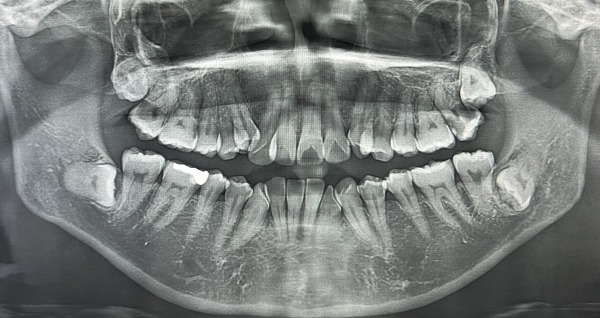

銀歯の隣の歯も黒く、虫歯になっていたため、エックス線写真を撮影しました。

治療前の歯は以下のような状態でした。